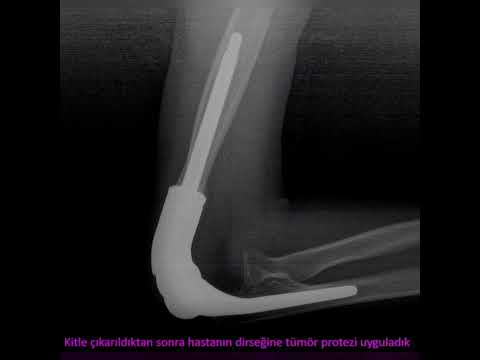

Tümör tedavisi nasıl yapılmalıdır?

Doğru tedavi ancak doğru tanı konarak yapılabilir. Tedavide temel nokta, çok iyi planlanmış bir ameliyattır. Bu ameliyat bazen basitçe yapılabileceği gibi bazen de damar cerrahı, plastik cerrah, omurga cerrahı ve genel cerrahi gibi diğer branşların da operasyona dahil olmasını gerektirecek tarzda ağır ve kompleks operasyonlar şeklinde de olabilir. Ancak işin başında ortopedik onkolog olmalı ve tüm süreci doğru şekilde yönetmelidir. Aksi halde hasta uzvunu ya da hayatını kaybedebilir.

İyi planlanmış ve doğru şekilde ameliyatı yapılmış bir hasta kendisini birkaç günde toparlar ve günlük yaşantısına döner. Ağır vakalarda bu süreç uzayabilir. Ne olursa olsun ameliyattan önce hastaya bilgi verilir ve olası komplikasyonlar detaylıca anlatılır. Hastanın kafasındaki soru işaretleri ameliyat öncesi giderilir. Aksi her durum başarı şansını düşürecektir.